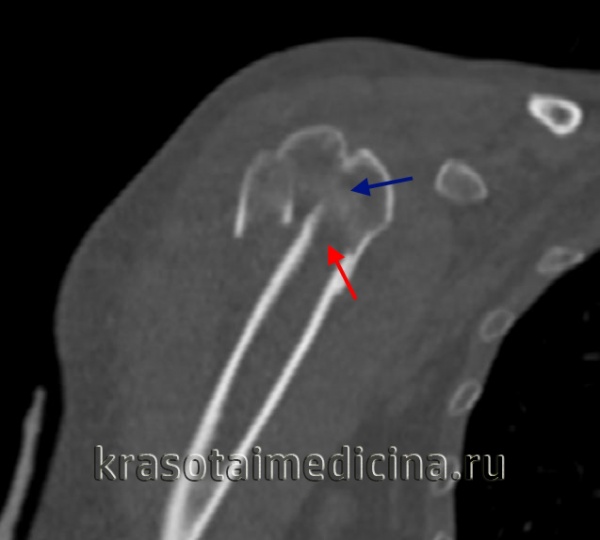

КТ плечевого сустава. Оскольчатый перелом хирургической шейки плечевой кости со смещением отломков. Дистальный отломок (красная стрелка) вколочен в проксимальный отломок (синяя стрелка).